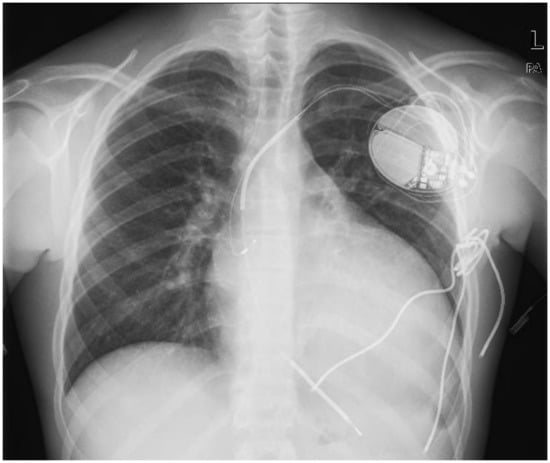

An epicardial defibrillation patch (Medtronic, Inc., ST Anthony, MN, USA) was placed on the left ventricular lateral wall, but again DFT testing was ineffective using the right ventricular (RV) coil to lateral patch as shock pathway. Another epicardial defibrillation patch was then placed on the inferior wall (Figure 2 left panel). In this case, DFT testing was effective with a defibrillation pathway between the two patches and the can. The subcutaneous multi-coli arrays were removed.

Figure 2.

Left panel. AP chest X-ray showing dual-chamber ICD connected to two epicardial patches (lateral and inferior). The defibrillation pathway is between the two patches and the can (red arrows). Figure 2 right panel. CT scan shows strong adhesion of the patches with the underlying myocardium.

In September 2012, the left lateral epicardial patch showed high impedance (>200 ohm), indicating it was damaged. The inferior patch–can shock pathway was then programmed.

Several options were considered. The first one was surgical removal and replacement of the broken epicardial patches, but this was considered too dangerous due to possible strong adhesions of the patches with the underlying myocardium, with consequent risk of myocardial rupture (Figure 2 right panel).